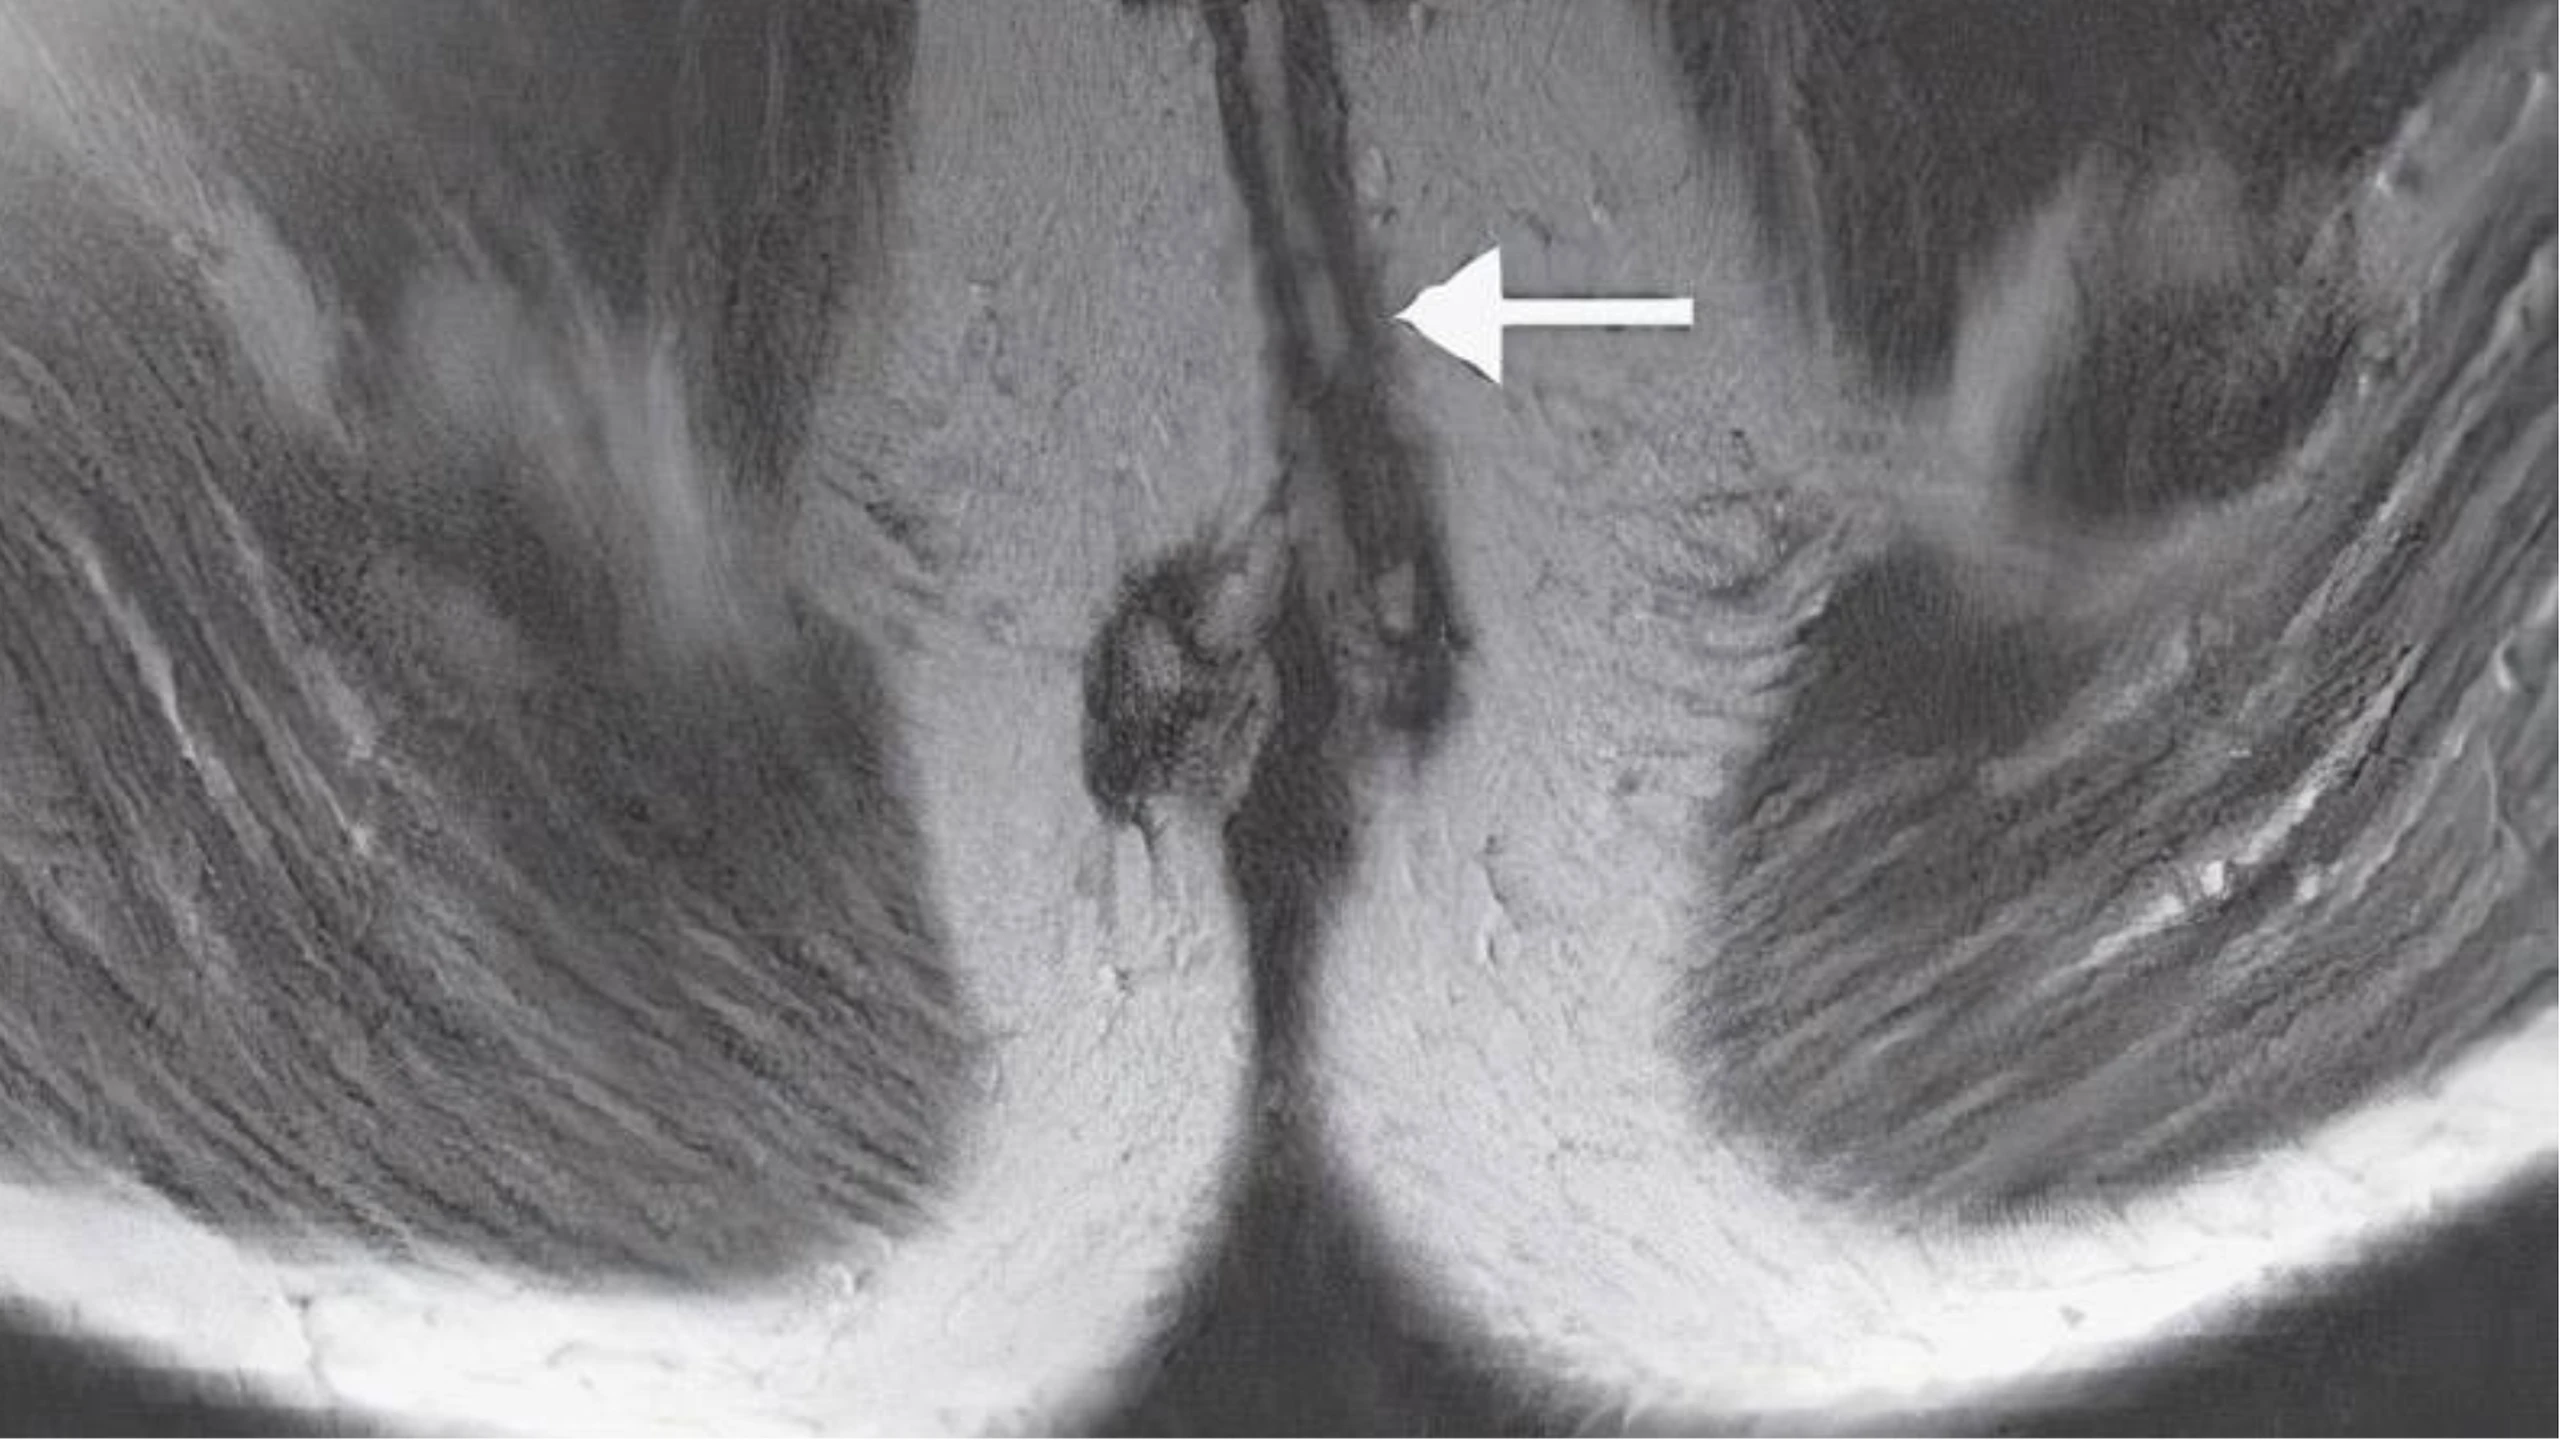

Da quanh hậu môn rất nhạy cảm, thường bị ngứa do nhiều nguyên nhân. Đôi khi vùng da này nhận được kích thích và bị bệnh nhân hiểu lầm rằng bị đau, do đó cần loại trừ các nguyên nhân gây đau khác (áp xe hay ung thư).

Ngứa hậu môn thường khác với cảm giác ngứa ở các vị trí khác trong cơ thể, thường là ngứa cục bộ, dữ dội và kéo dài, càng gãi càng ngứa gây nóng, rát và đau nhức hậu môn. Ngứa và kích thích bên trong hay xung quanh hậu môn có thể là tạm thời nhưng có thể kéo dài.

Ngứa hậu môn thường cục bộ, nhưng cũng có thể lan sang bộ phận sinh dục như sau bìu (nam giới), âm hộ, môi lớn, môi bé và âm đạo (nữ giới). Ở nữ giới, do khoảng cách giữa hậu môn và âm đạo, niệu đạo rất ngắn nên ngứa hậu môn rất dễ lây lan sang bộ phận sinh dục và hệ tiết niệu.

Ngứa hậu môn không phải là một bệnh nguy hiểm nhưng làm người bệnh cảm thấy rất khó chịu, tự ti, lúng túng khi làm việc hay giao tiếp.